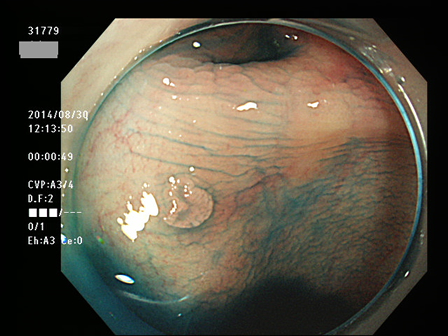

上記100名より抽出した平坦・陥凹型腺腫(=癌化の危険が高いが見落としやすい病変)の内視鏡写真

31764 31765 31766 31767 31768 31769 31771 31774 31776 31777 31778 31779